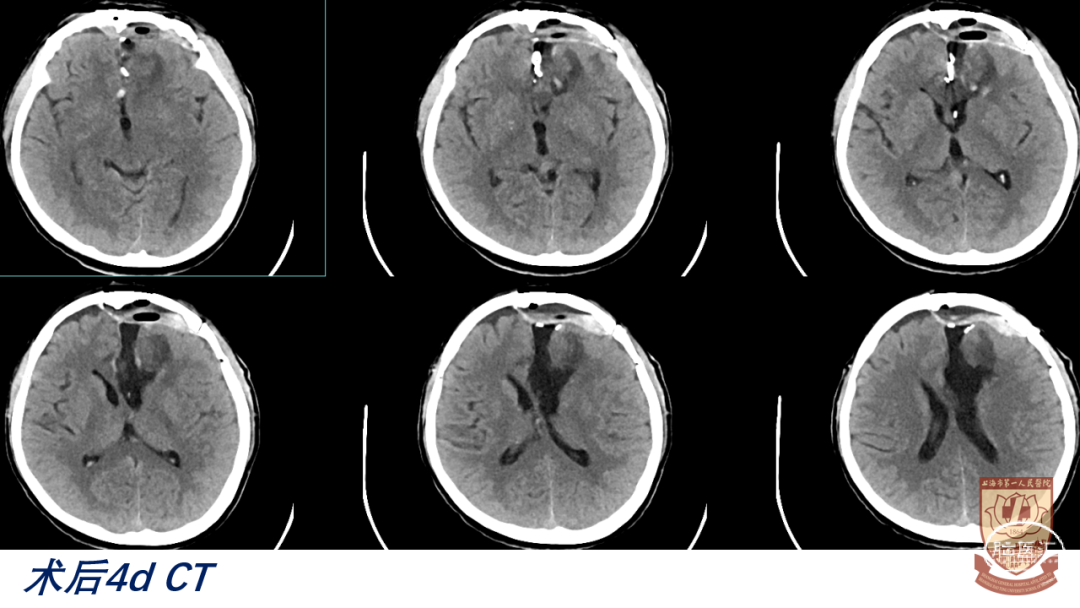

04

结果

术后GCS15分,言语正常,肢体感觉、肌力正常

脑室引流管顺利夹管、拔除

正常出院,无明显神经功能障碍